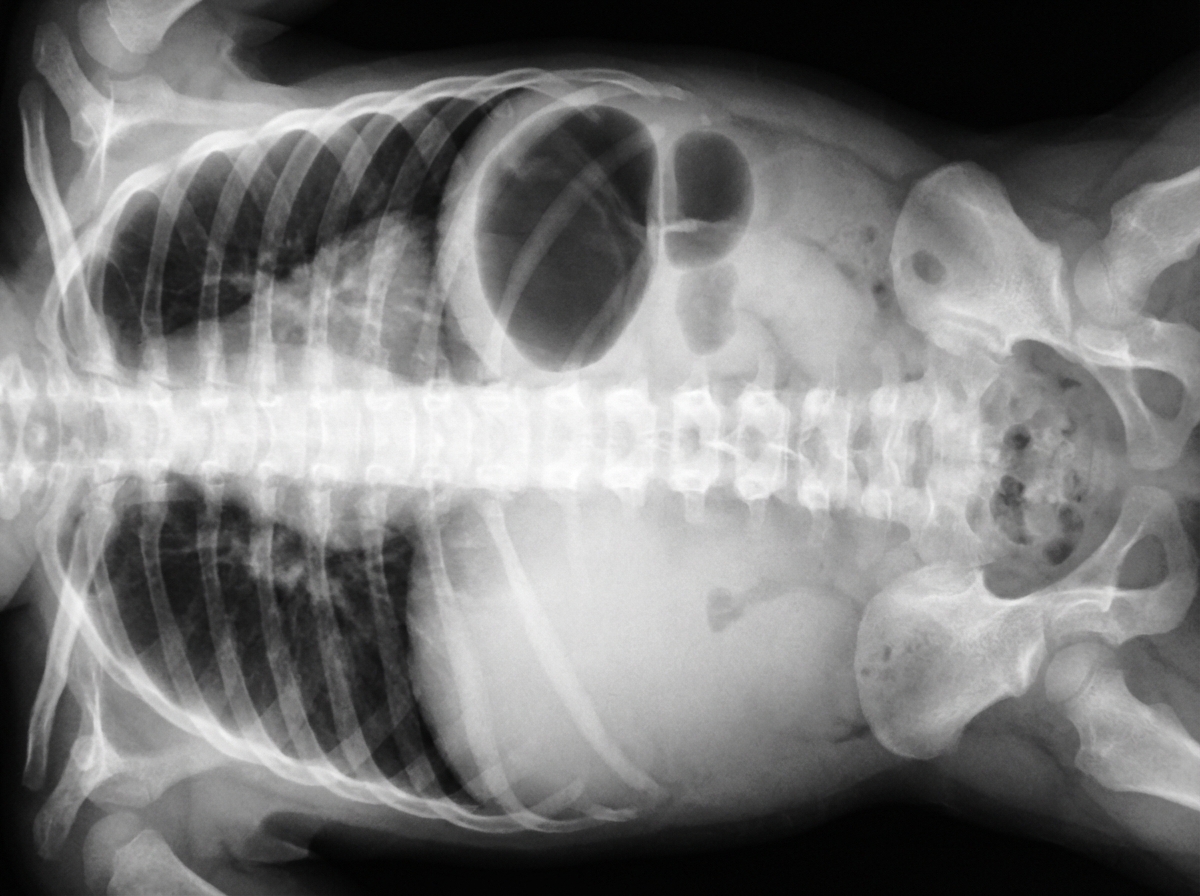

A female newborn delivered at 38 weeks’ gestation is evaluated for abdominal distention and bilious vomiting 24 hours after delivery. The pregnancy and delivery were uncomplicated. She appears lethargic and her fontanelles are sunken. An x-ray of the abdomen is shown. This infant most likely has a congenital obstruction affecting which of the following anatomic structures?